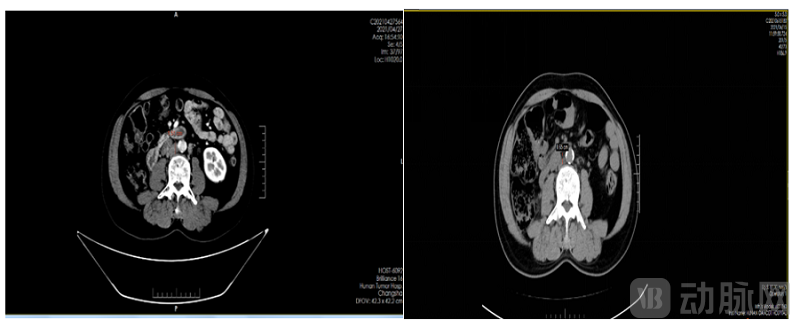

后入组MRG002 治疗经至少一线全身化疗的HER2阳性无法手术切除的局部晚期或转移性尿路上皮癌的开放、单臂、多中心 II 期临床试验,接受MRG002单药治疗,经过2周期治疗后其中非靶病灶全部消失,一个靶病灶消失,另一个靶病灶腹膜后淋巴结缩小至6.5mm,具体见下图:

图1. 膀胱肿块基线(左)和首次用药后6周膀胱肿块(右)